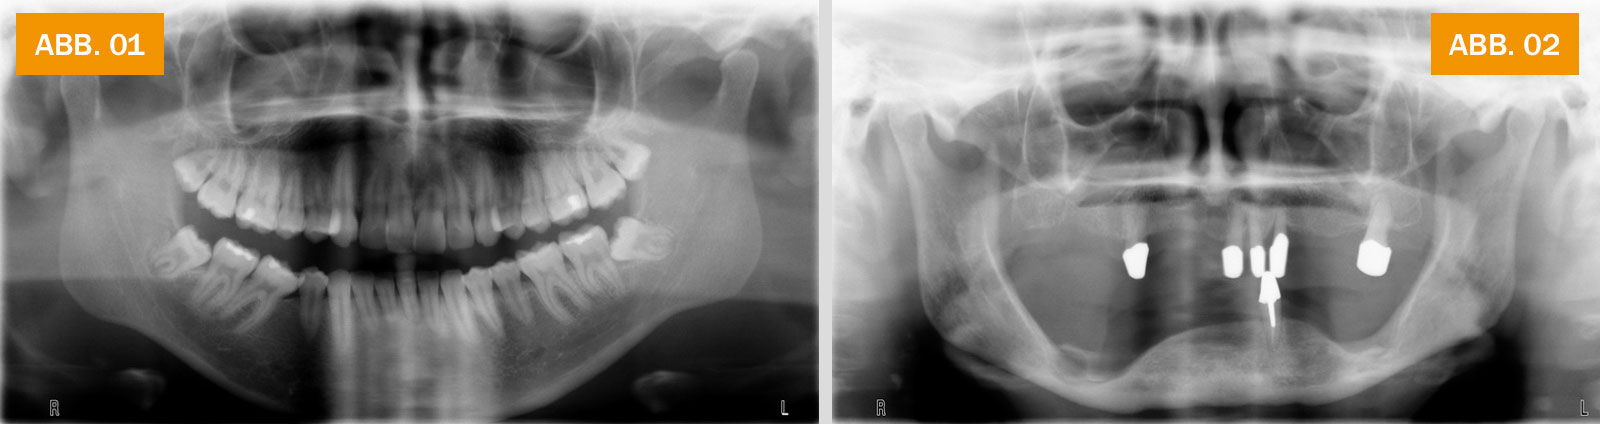

ABB. 01: Röntgenbild eines Jugendlichen mit voll bezahntem Ober- und Unterkiefer. Die Kieferknochen werden ständig belastet und sind stark ausgebildet.

ABB.02: Röntgenbild eines älteren Menschen mit wenigen verbliebenen Zähnen. In zahnlosen Bereichen haben sich der Ober- und Unterkiefer deutlich zurückgebildet.